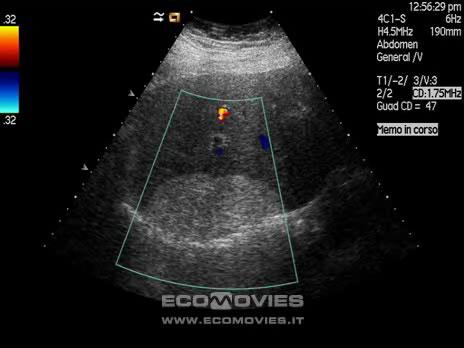

Portal Hypertension

Portal Hypertension

Budd-Chiari

Life threatening emergency

Portal vein Thrombosis - cavernous transformation

replacement of the normal single channel portal vein with numerous tortuous venous channels.